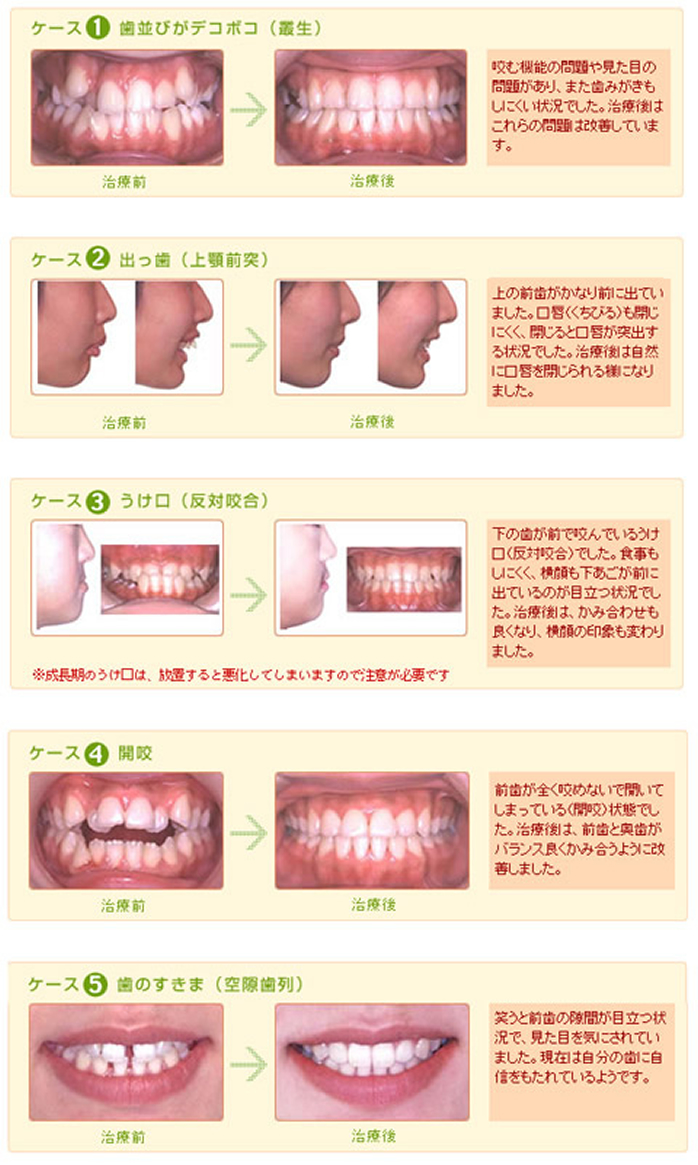

矯正治療 橋口歯科 赤坂ガーデンシティ

少回数ですむ悪い歯並び治療写真 ザ ホワイトデンタルクリニック

こんな歯並びは要注意 みやわき矯正歯科クリニック 宇部市 山口市

よくない歯並びの種類とその及ぼす影響とは 矯正 香川県 香川矯正センター たくま歯科は世界水準の治療

あなたの歯並びはどれですか その悪い原因 治療方法を比較